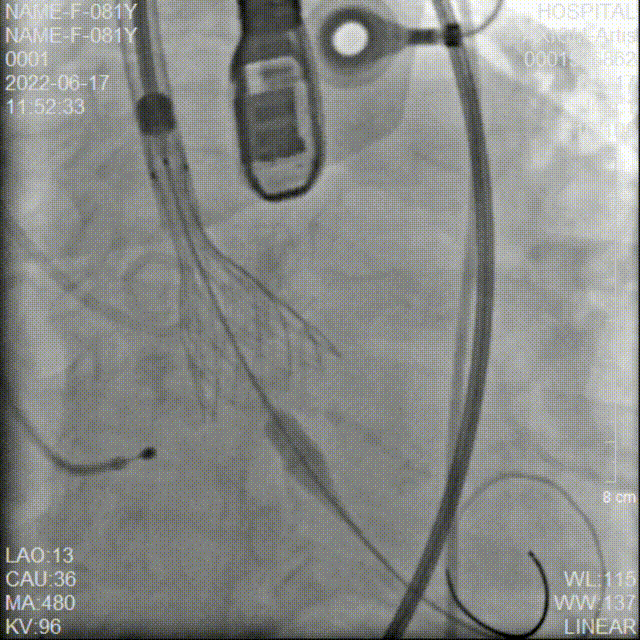

冠脉造影检查